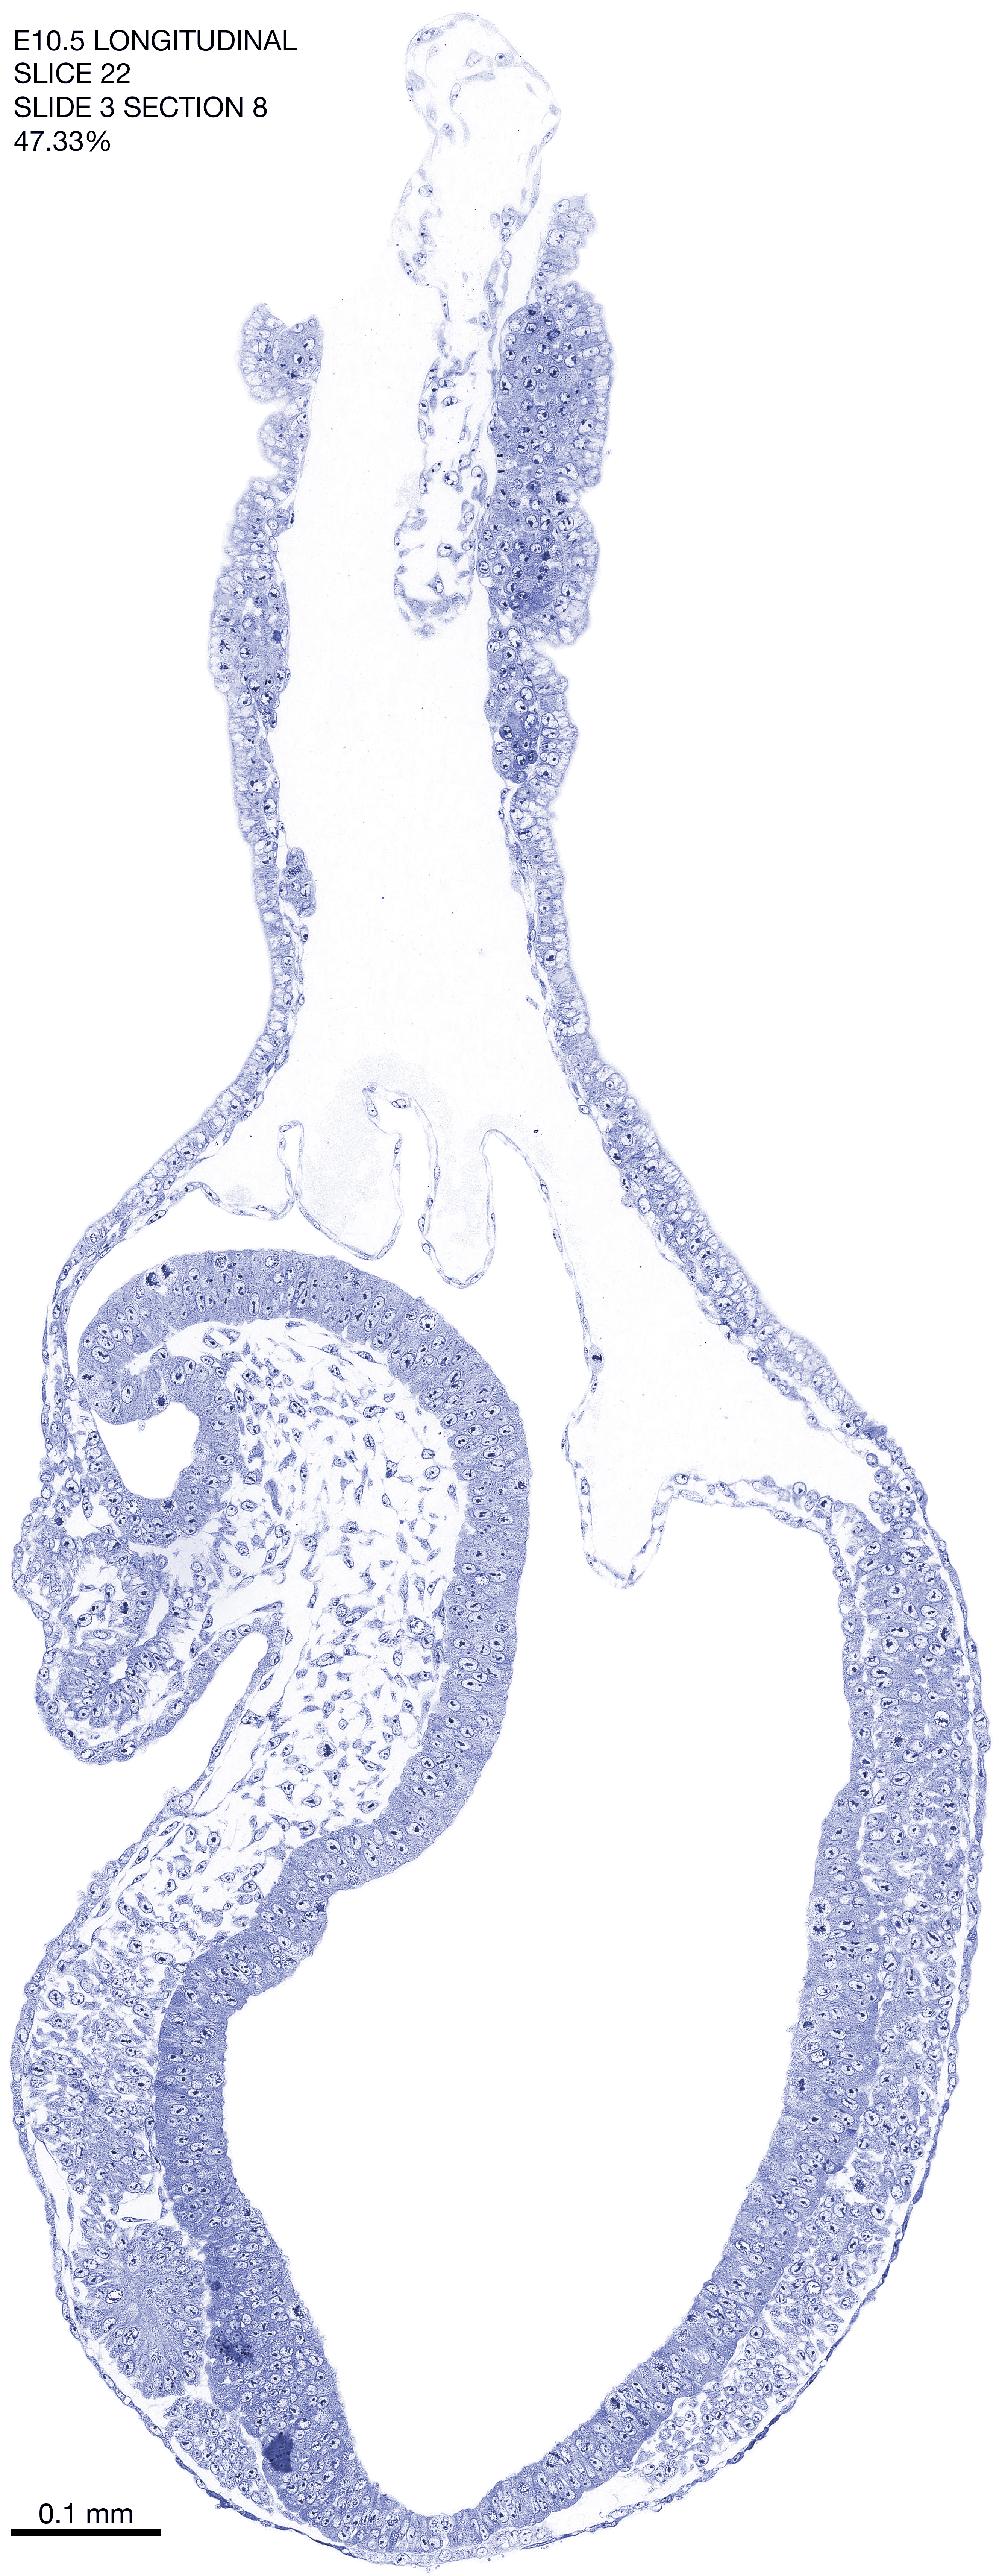

E10.5 Longitudianal Archive This page contains jpg files of ALL SLICES (each 3µm thick) that were scanned of the E10.5 longitudinally cut specimen. Download: Large | High Res Download: Large | High Res Download: Large | High Res Download: Large | High Res Download: Large | High Res Download: Large | High Res Download: Large | High Res Download: Large | High Res Download: Large | High Res Download: Large | High Res Download: Large | High Res Download: Large | High Res Download: Large | High Res Download: Large | High Res Download: Large | High Res Download: Large | High Res Download: Large | High Res Download: Large | High Res Download: Large | High Res Download: Large | High Res Download: Large | High Res Download: Large | High Res Download: Large | High Res Download: Large | High Res Download: Large | High Res Download: Large | High Res Download: Large | High Res Download: Large | High Res Download: Large | High Res Download: Large | High Res Download: Large | High Res Download: Large | High Res Download: Large | High Res Download: Large | High Res Download: Large | High Res Download: Large | High Res Download: Large | High Res Download: Large | High Res Download: Large | High Res Download: Large | High Res Download: Large | High Res Download: Large | High Res Download: Large | High Res Download: Large | High Res Download: Large | High Res Download: Large | High Res Download: Large | High Res Download: Large | High Res Download: Large | High Res Download: Large | High Res Download: Large | High Res Download: Large | High Res Download: Large | High Res Download: Large | High Res Download: Large | High Res Download: Large | High Res Download: Large | High Res Download: Large | High Res